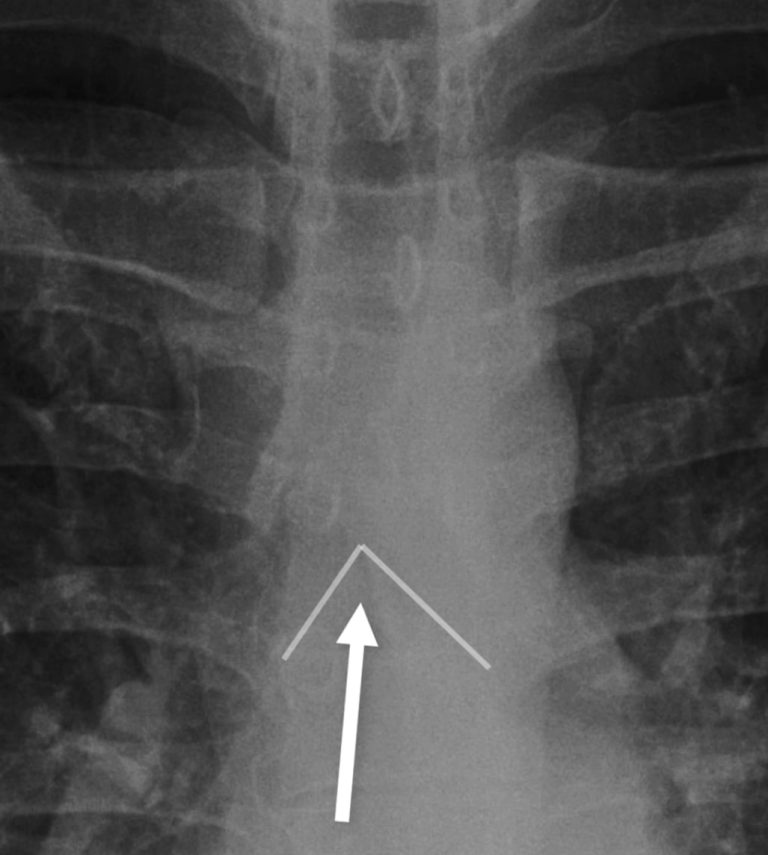

C: Carina

This is where the trachea bifurcates into right and left main bronchi.

The angle of bifurcation should be about 60–70° and certainly no more than a right angle. A splayed carina most commonly suggests left atrial enlargement but can represent node enlargement.

As left atrial enlargement is fairly common by a certain age splaying of the carina can be considered a ‘soft sign’ so I usually use this as corroborative information to increase my confidence if there are other signs of mediastinal node enlargement such as loss of the AP window and loss of the paratracheal stripe.

Review the angle of the carina and make sure it is not more than a right angle.